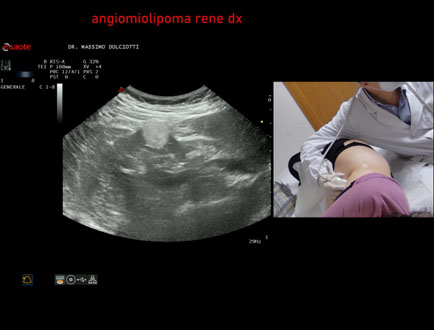

Data inserimento: 03/04/2026

Ecografia del: 12/03/2026

Strumento: Esaote MyLab Eight

Sonda: Convex Multifrequenza 1-8 MHz

Età Paziente: F 66 anni

Motivazione dell'esame: follow up per angiomiolipoma renale destro

Commento all'esame: le immagini ed il video documentano al rene destro, in sede corticale polo inferiore, immagine iperecogena, a margini definiti, delle dimensioni di 25 x 23 mm, senza segni di vascolarizzazione, da ricondurre, come prima ipotesi, ad angiomiolipoma.

Conclusioni: angiomiolipoma del rene destro (angiomyolipoma of the right kidney).

In collaborazione: Dr.ssa Marica Manfredi - Ancona, Dr. Ilir Qose - Ancona

Presentazione: Dr. Massimo Dolciotti - Ancona

Elaborazione digitale: Andrea Dini - Ancona